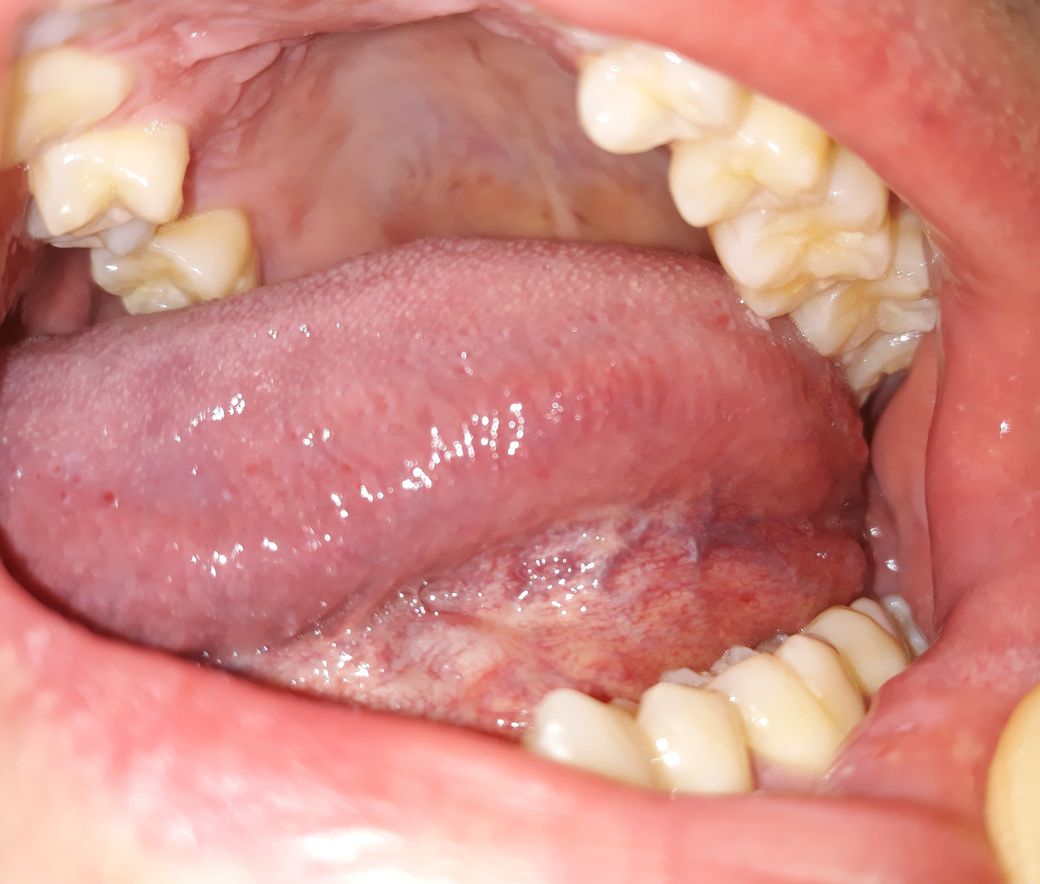

양치하다가 혓바닥 옆쪽 아래를 봤는데 잔핏줄도 많이 보이고 중간에 색깔도 군데군데 누런거같기도한데 만져보니깐 부드럽고 통증이나 불편한건 없습니다. 괜찮은건가요?

• 1번 째 사진

입 구석구석을 살펴보셨네요. 사진 올려주신 것만 봐서는 특별한 이상은 없어 보입니다. 증상도 없으니 괜찮다고 보셔도 되구요.